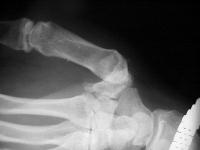

Advanced degenerative changes of the joint: loss of joint space, subchondral sclerosis, large osteophyte, erosions, all with preservation of the adjacent joints.